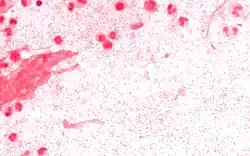

Clinical diagnosis of invasive H. influenzae infection (infection that has spread to the bloodstream and internal tissues) is typically confirmed by bacterial culture, latex particle agglutination tests, or polymerase chain reaction tests on clinical samples obtained from an otherwise sterile body site. In this respect, H. influenzae cultured from the nasopharyngeal cavity or throat would not indicate H. influenzae disease, because these sites are colonized in disease-free individuals.[37] However, H. influenzae isolated from cerebrospinal fluid or blood or joint fluid would indicate invasive H. influenzae infection. Microscopic observation of a Gram stained specimen of H. influenzae will show Gram-negative coccobacillus. The cultured organism can be further characterized using catalase and oxidase tests, both of which should be positive. Further serological testing is necessary to distinguish the capsular polysaccharide and differentiate between H. influenzae b and nonencapsulated strains.